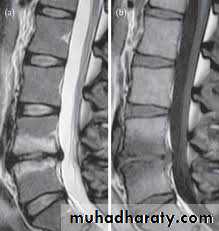

MRI

It is superior to computed tomography (CT) because of its tissue contrast and multi planar capabilities.General objectives of treatment

CT, CT- Myelography

MRl